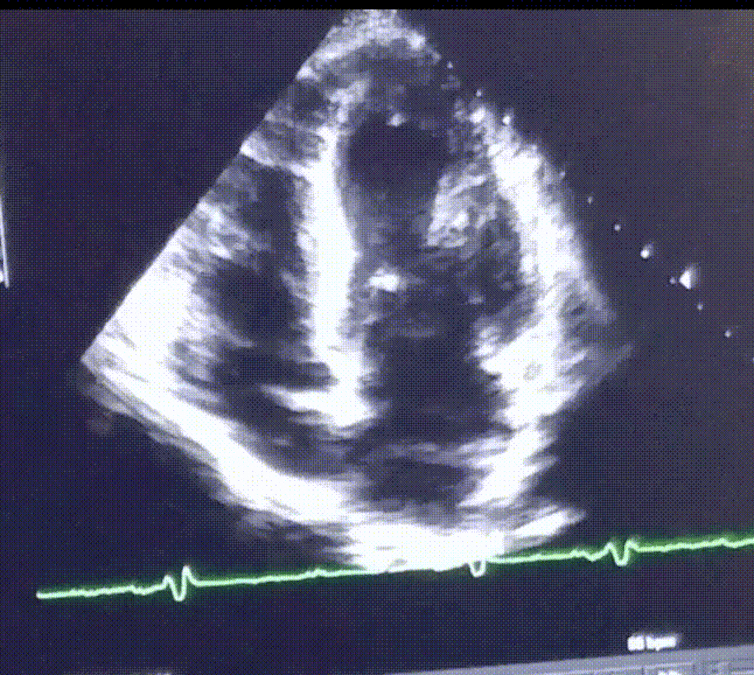

When people exceed these guidelines, the heart may remodel itself in response – that is, it begins to change its size and shape. As a result, heart function may also change. These changes in heart structure and function among people who engage in high levels of exercise are referred to as the athletic heart, or athlete’s heart. Athletic heart doesn’t necessarily cause problems, but in some people it can increase the risk of certain heart issues.

It is important to distinguish between dynamic and static exercise because the heart adapts differently according to the type of exercise you engage in over time. Dynamic exercise increases the volume of blood pumping through the heart and can cause the heart to become enlarged, or dilated, over time. Static exercise increases the amount of pressure on the heart and can also cause it to become enlarged over time but with thickened walls.

Among runners, for example, the heart remodels itself in response to having to pump a high volume of blood. As a result, the chambers of the heart enlarge to hold and pump more blood. Among weightlifters, the heart remodels itself by thickening in response to the increase in pressure applied on the heart.